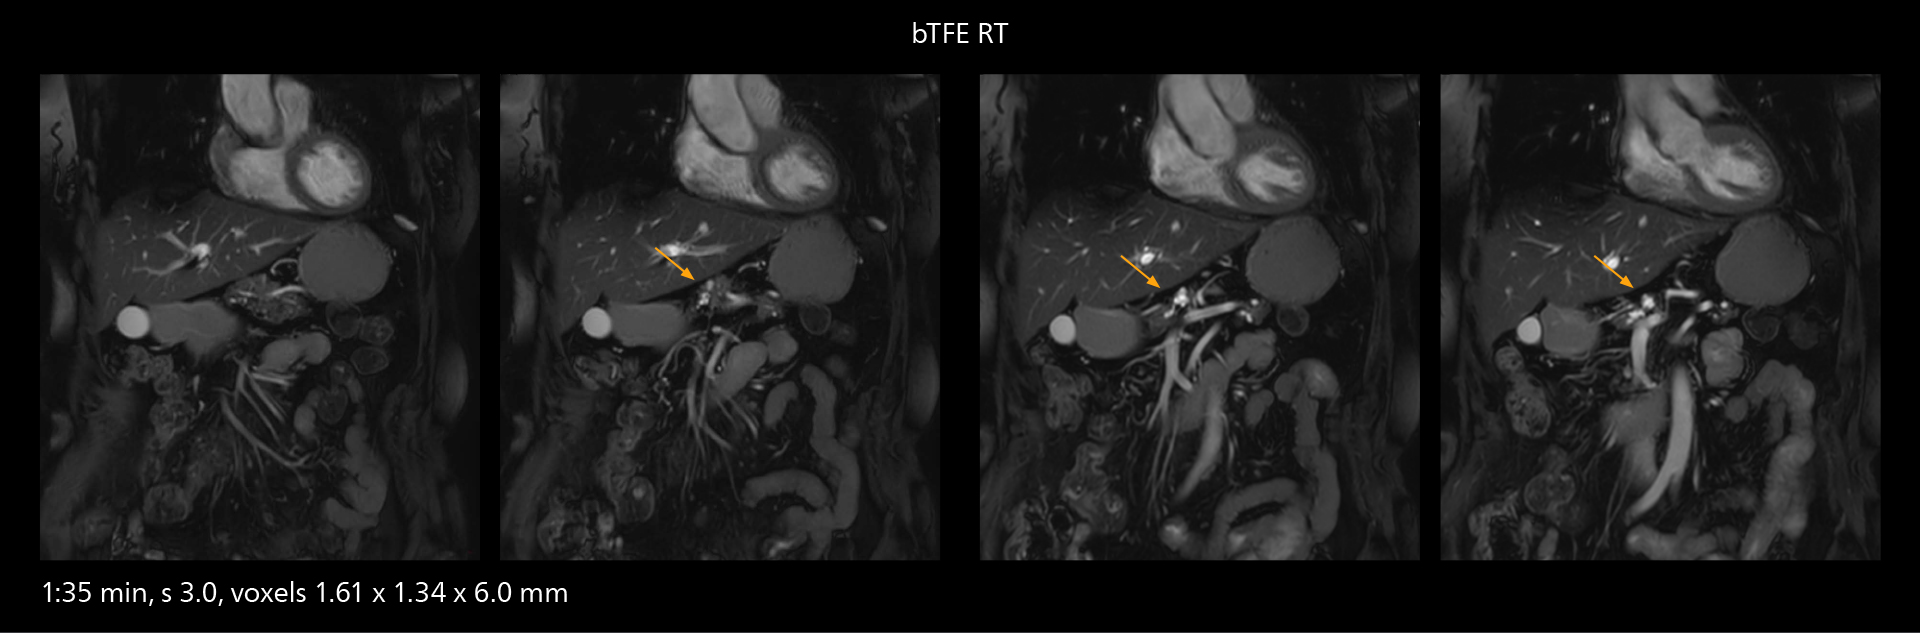

SmartPath to Elition X comes with Smart Workflow technologies that support technologists and can save them time. VitalEye for touchless patient sensing is one example. “The implementation of VitalEye respiratory synchronization has had a significant impact,” says MR technologist Yoshihiro Otsu, Chief of the Radiological Department. “It not only improves workflow, but it also has increased the quality of examinations. Particularly for the large number of MRCP examinations performed in this hospital, VitalEye has increased the possibility to obtain sharp images with less blurring. Clinicians here really appreciate this improvement in MRCP image quality.” The VitalScreen on the scanner has helped reduce the risk of patient misidentification. “It allows patient information to be viewed in the magnet room when standing next to the patient,” he says. “And the automated patient centering in the magnet is very useful as well.” Apart from reducing stress for technologists, Smart Workflow helps improve respiratory synchronization and reduce examination stress for the patient.

VitalEye has increased the possibility of obtaining sharp images with less blurring. Clinicians here really appreciate this improvement in MRCP image quality.”

Yoshihiro Otsu

With SmartPath to Elition X, the MRCP examinations at Sannodai Hospital benefit from VitalEye: respiratory synchronization is possible without respiratory belt positioning and image quality is excellent.